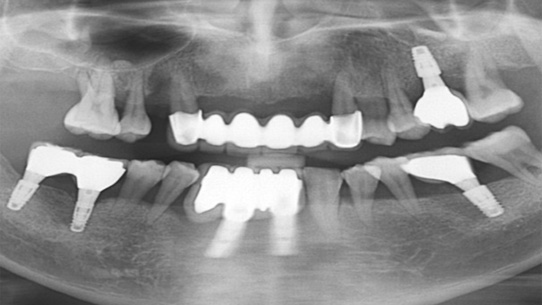

심한 염증과 기존 보철물의 오염상태가 심해 임플란트 17개를 진단받고 내원하신 환자분, 특히 앞니부분의 치조골이 많이 약해져 흔들림이 심하여 바로

치주치료를 시행하였습니다. 치주치료 2주 후 앞니 잇몸이 개선되어 발치 하지 않고 교정 유지장치를 이용하여 흔들림을 보완하였습니다.

오염된 보철물을 제거하고 임플란트 11개를 식립하였습니다.

심한 염증으로 치아가 흔들리는 상태

앞니 흔들림을 보완하는 유지장치 부착